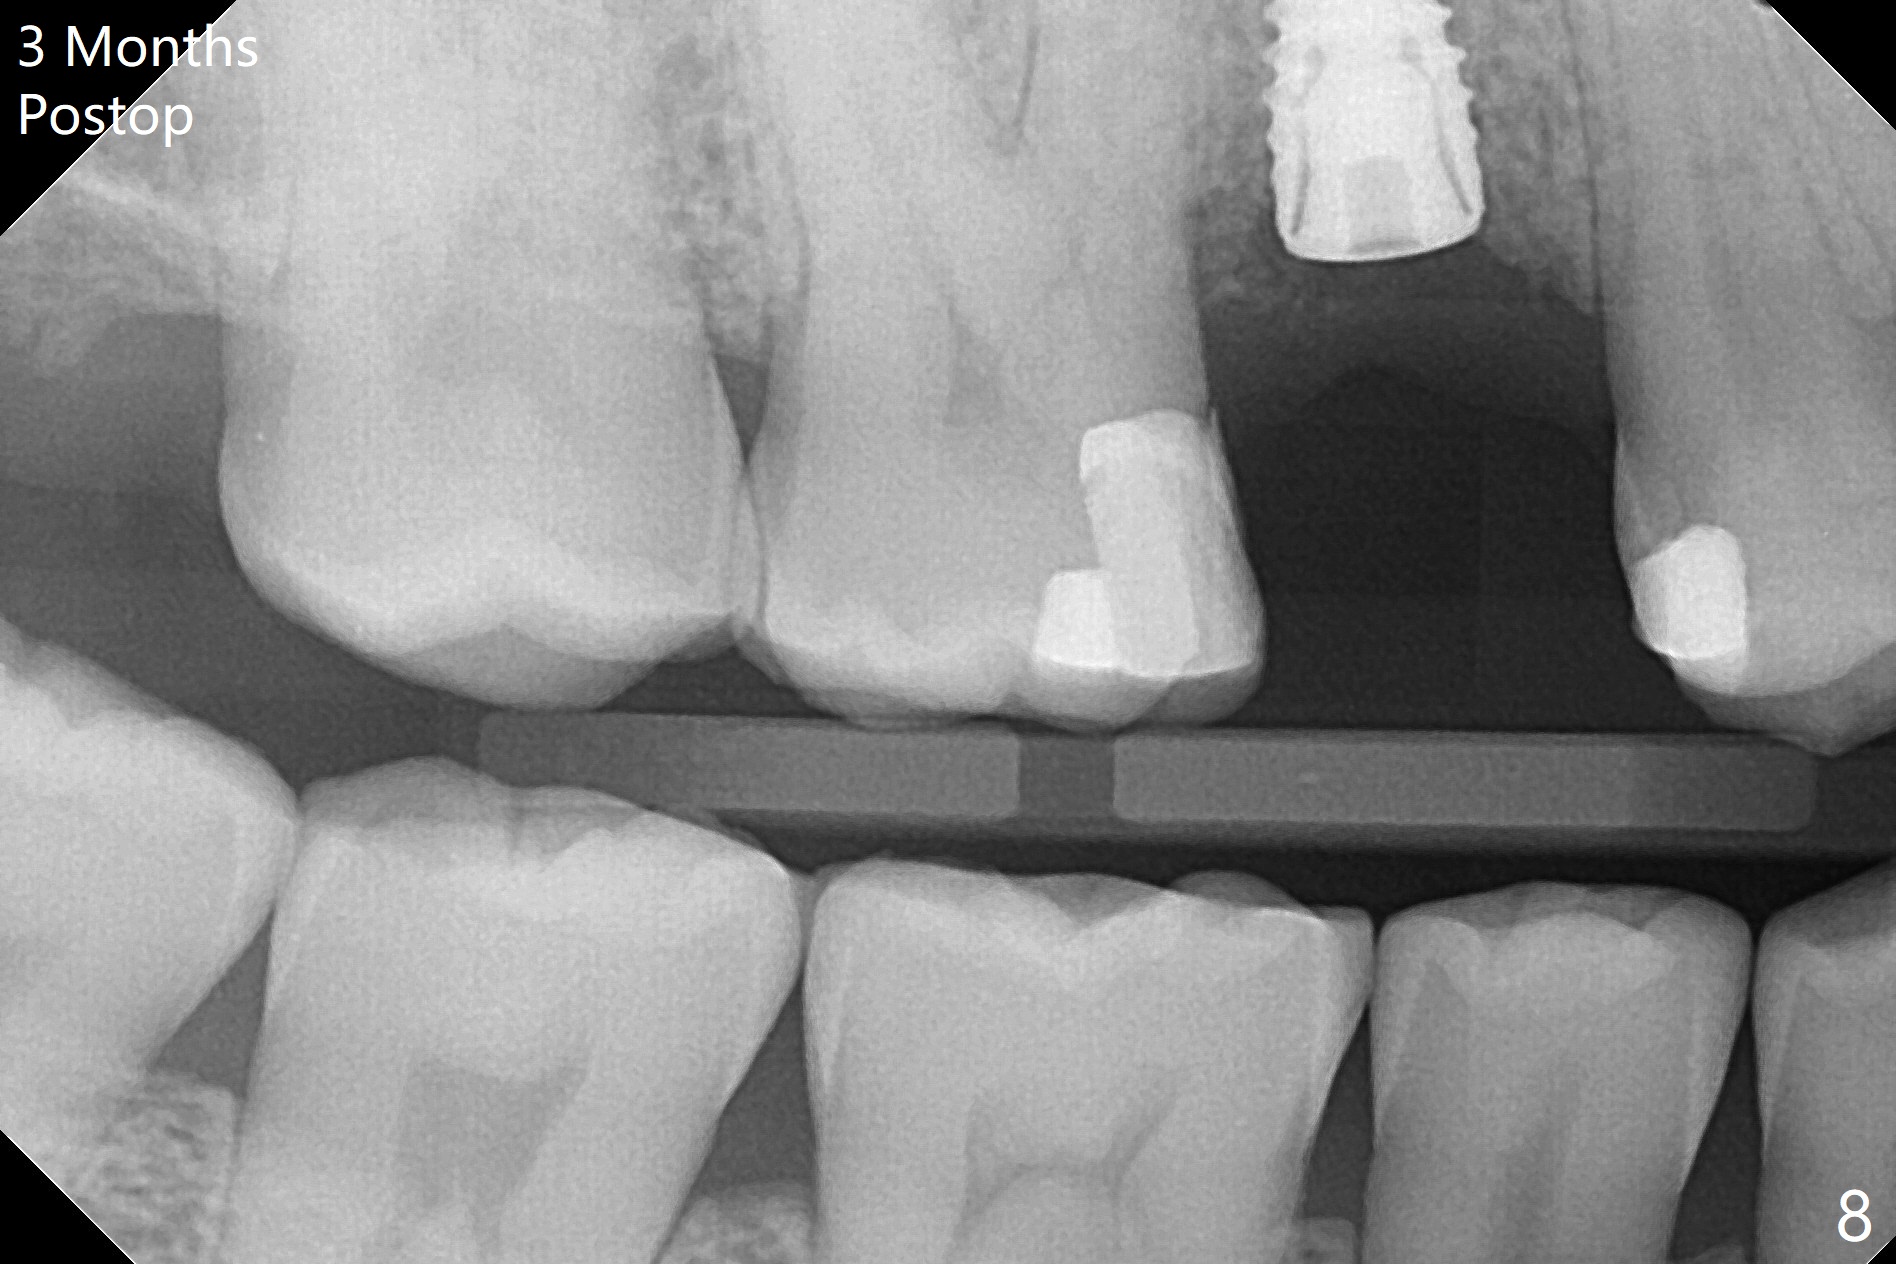

尽管没有任何症状,右上5牙冠粘固后2年5个月,牙冠与基台取出(没有使用扳手,说明基台未完全就位),切开,去除少量肉芽组织,仍然发现植体螺纹暴露(图一),使用一种叫I Brush 钛合金刷子清洁后,放置粘性骨块(图二: S),它坐在牙槽嵴上仿佛非常安稳,多么象马鞍(Saddle)。覆盖一张PRF膜和一小张Cytoplast(不可吸收膜,Osteogenics (company) 图三:箭头),使用PTFE缝线(与Cytoplast同样一种材料)缝合。术后即刻根尖片显示骨粉服服帖帖地坐落在植体和牙槽嵴上(图四:*)。最后覆盖牙周敷料。后者术后十天左右脱落,伤口愈合正常,颊侧瘘道仿佛消失,颊侧骨壁好像不再凹陷了(图五,六)。术后5周,膜已经脱落,缝线撤除后,伤口好像二期愈合,但愿肉芽组织下面骨粉尚未损失太多。术后三个月根尖片显示骨粉减少(图八)。不可吸收膜脱落可能造成骨粉流失。应该做减张缝合。术后4.5个月颊侧骨壁又凹陷(图九:箭头,需要decortication),但是uncover时植体周围都有骨质包绕,术后咬翼片也证明近中,远中骨质接触植体(图十:由于找不到合适愈合基台,直接放置基台和牙冠)。粘固后2.5个月虽然颊侧骨板凹陷,但是没有植体周围炎迹象(图十一)。